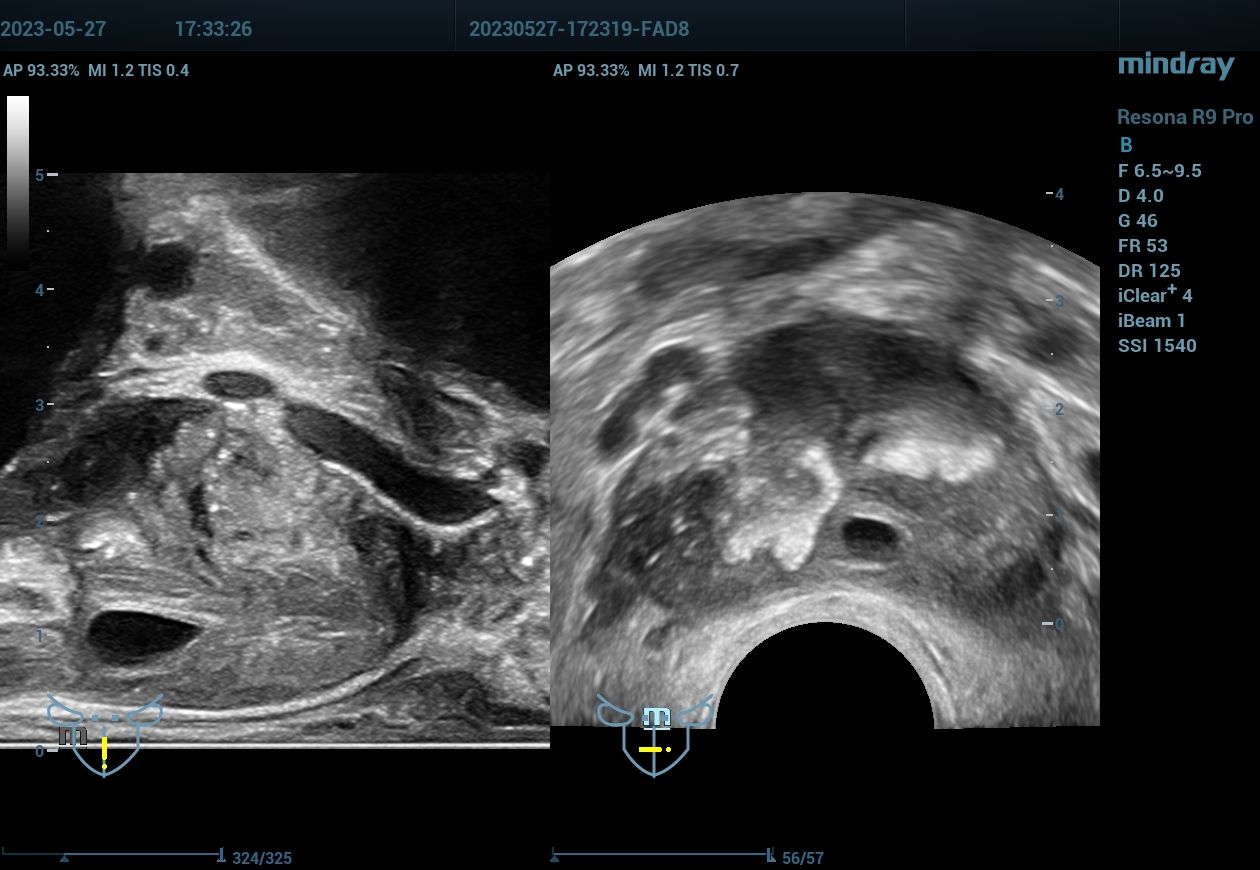

病例,射精管囊肿:双平面探头检查,颠覆经腹探头诊断(前列腺囊肿),柳州市人民医院2023

病例,射精管囊肿:经直肠双平面探头检查,颠覆经腹探头诊断(前列腺囊肿)。还可以观察到精囊腺肿胀。柳州市人民医院,2023年